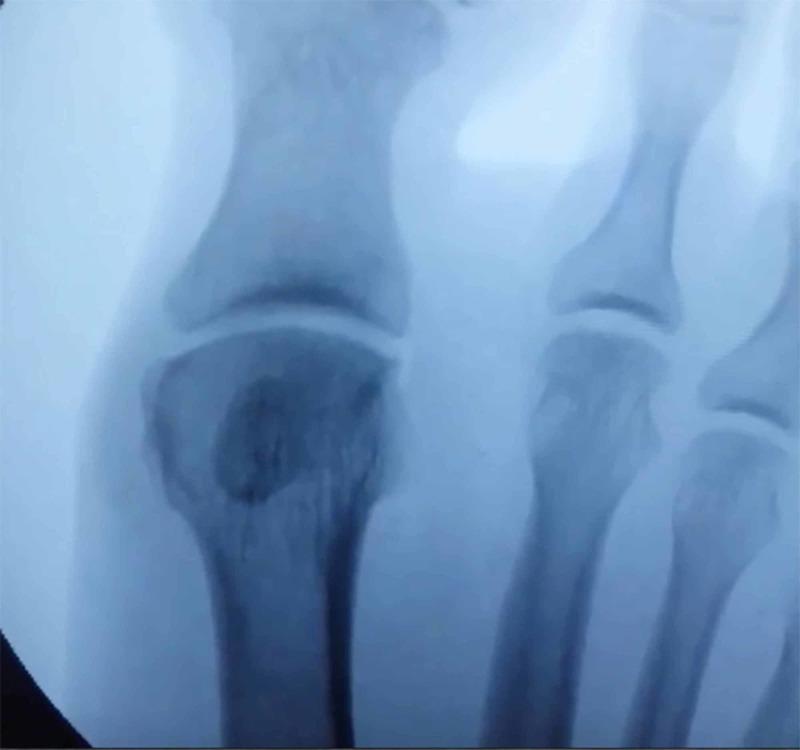

Background Pathologic conditions of the sesamoids can be a source of disabling pain for patients, particularly during toe-off. Some underlying causes include osteonecrosis, inflammation, arthritis, and fracture. Nonoperative treatment is the initial standard of care, and has demonstrated satisfactory outcomes overall; however, operative management may be indicated in cases of pain refractory to conservative management. Sesamoidectomy is an uncommon procedure with risk of potential complications, but may be warranted in select cases of failed nonoperative treatment. Methods A retrospective chart review was conducted at one institution from 2009 to 2018. Twelve patients diagnosed with fibular sesamoiditis were treated with sesamoidectomy. Baseline patient demographics as well as postoperative outcomes were recorded. Results All 12 patients underwent fibular sesamoidectomy using the plantar approach following which their symptom (pain) resolved. Average follow-up for this cohort was 35 months. Of the sample, two patients experienced transient neuritis, one patient developed a superficial infection, and one had painful postoperative scarring. Hallux varus deformity was not observed in any patients. Conclusion Fibular sesamoidectomy may be a safe, viable procedure for patients with sesamoiditis who fail conservative measures.

背景 籽骨的病理状况可能是患者致残性疼痛的一个来源,尤其是在蹬离期。一些潜在病因包括骨坏死、炎症、关节炎和骨折。非手术治疗是初始的标准治疗方法,总体上已显示出令人满意的结果;然而,对于保守治疗无效的疼痛病例,可能需要进行手术治疗。籽骨切除术是一种不常见的手术,存在潜在并发症的风险,但在某些非手术治疗失败的病例中可能是必要的。方法 2009年至2018年在一家机构进行了一项回顾性病历审查。12例被诊断为腓侧籽骨炎的患者接受了籽骨切除术。记录了患者的基线人口统计学数据以及术后结果。结果 所有12例患者均采用足底入路进行了腓侧籽骨切除术,术后症状(疼痛)均得到缓解。该队列的平均随访时间为35个月。在样本中,2例患者出现短暂性神经炎,1例患者发生浅表感染,1例患者术后瘢痕疼痛。所有患者均未观察到拇内翻畸形。结论 对于保守治疗失败的籽骨炎患者,腓侧籽骨切除术可能是一种安全、可行的手术。